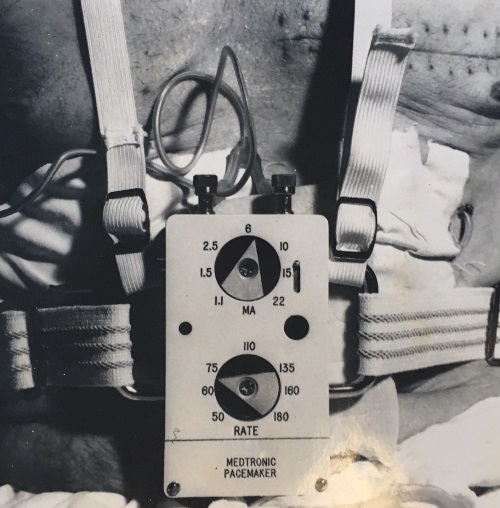

Pacemakers: Past and present Blog Posts

Pacemakers have evolved over the years by becoming more compact and sophisticated, but they still operate the same way in keeping the heart beating at a regular rate.